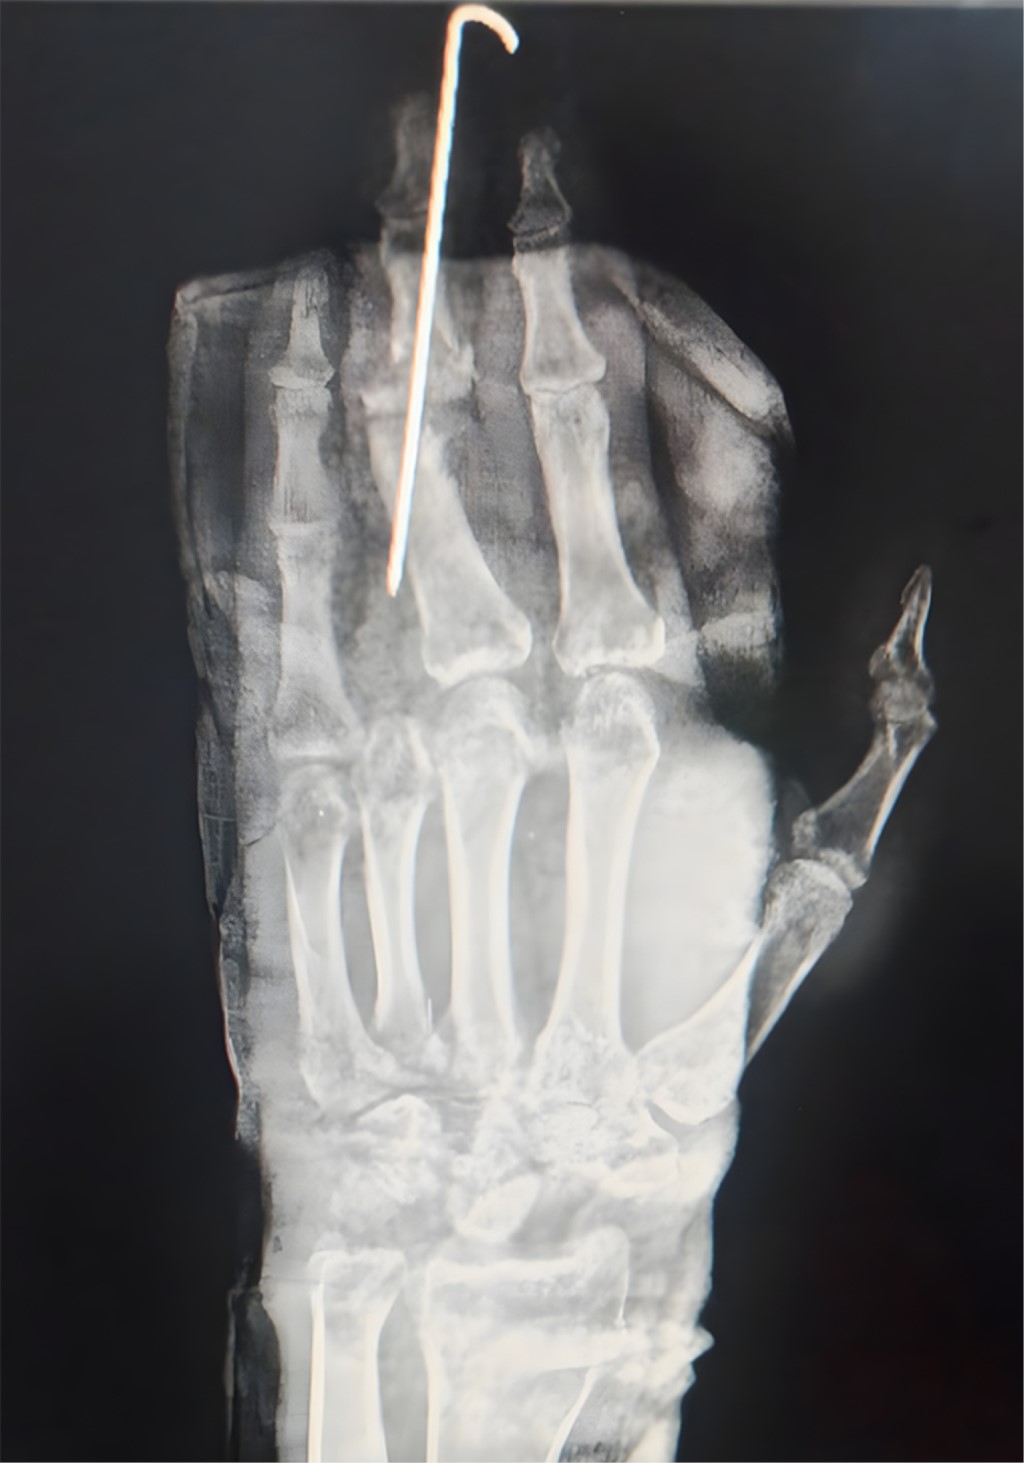

Durante su estancia se manejó con impregnación antibiótica más analgesia; posterior a la impregnación antibiótica, pasa a procedimiento definitivo donde se realizó carpectomía de muñeca izquierda (Figuras 4 y 5) con artrodesis de articulación interfalángica de F2-F3 tercer dedo (Figura 6) más tenorrafia de extensor propio de quinto dedo (Figura 7) y colgajo de herida cruenta en quinto dedo (Figura 8).

Técnica quirúrgica. Se realizó con vía de abordaje longitudinal posterior (dado a que presenta mejor exposición y disminuye el riesgo de presentar lesiones nerviosas), usando como referencia el tubérculo de Lister, se liberan los bordes cutáneos del retináculo extensor, liberando entre el tercer y cuarto compartimento extensor posterior, observando la cápsula articular, identificamos el interóseo posterior de lado interno al tubérculo de Lister, realizamos una capsulotomía en T con incisión transversal a 2 mm del borde radial de la inserción capsular y, paralela a él, la incisión vertical en el eje del tercer metacarpiano; exploramos la integridad de las fosetas del semilunar y del escafoides para poder realizar la resección de la primera fila (realizando tracción y flexión palmar), de este modo podemos realizar el retiro de los huesos de la primera fila del carpo (teniendo cuidado en no lesionar el cartílago del hueso grande); iniciamos con el retiro del semilunar, posterior del piramidal y finalizamos con el escafoides; después de eso se corrobora adecuada flexo-extensión de la muñeca; continuamos con el cierre de la capsulotomía en T, así como del ligamento anular, tejido celular subcutáneo y piel (Figuras 9 y 10).5